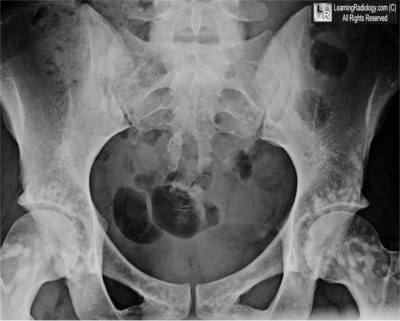

What is the most likely diagnosis?

- 37 year-old female with abdominal pain

- Osteoblastic breast metastases

- Dermoid of the ovary

- Osteopoikilosis

- Pelvic fracture

- Multiple myeloma

Additional Images - Axial CT scan of the pelvis